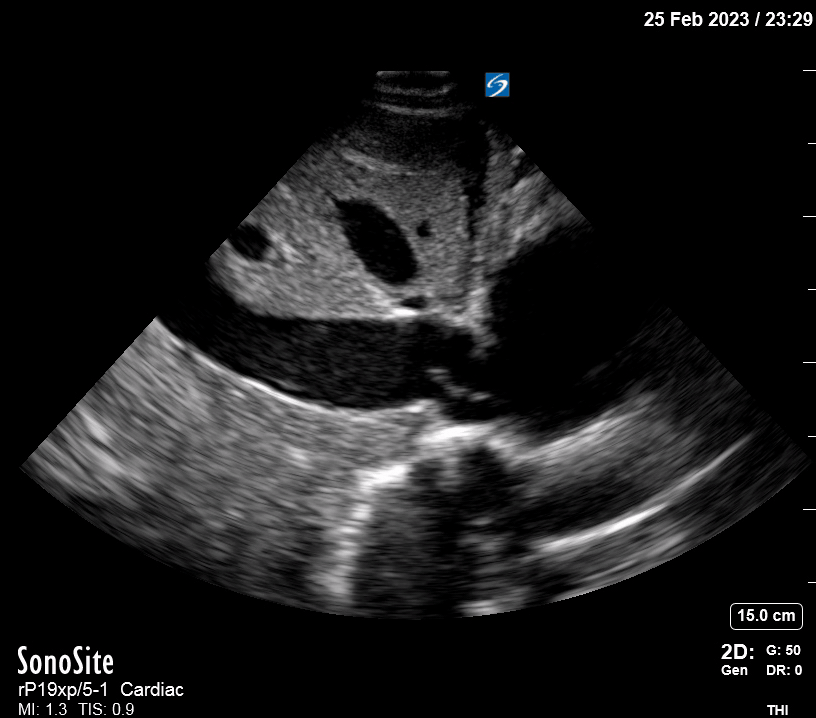

Equality: is the RV dilated or significantly impaired?

Normally, the RV is a low-pressure, thin-walled, high-compliance chamber that wraps anteriorly around the muscular, cone-shaped LV. The normal RV : LV diameter ratio is 0.6 : 1.

When the pulmonary artery pressure rises, the RV will dilate, altering the normal RV:LV ratio. Although sacrificing sensitivity, the use of equality (1:1 ratio) as a cutoff can achieve a specific estimation of RV strain. If imaged correctly by a trained operator, the presence of an RV:LV ratio > 1 is highly specific for RV strain.

RV dilation can be acute, chronic, or acute-on-chronic. However, in patients presenting with undifferentiated chest pain, shortness of breath, hypotension or syncope, the presence of any RV dilation should raise suspicion for acute pulmonary embolism (PE). Furthermore, in a patient in shock, the presence of RV strain may signal the need for aggressive therapy – emergency thrombolysis.

THE VIEWS

The A4C view provides an accurate chamber size comparison. However, achieving a proper A4C view (avoiding foreshortening or ballooning, and visualising the four chambers with a vertically oriented interventricular septum) can be a challenging exercise of image acquisition. Additionally, the PSAX view at the level of the papillary muscles shows both LV and RV side by side and is useful to assess function and size. When RV pressure is high, the septum will be pushed and flattened towards the LV, resulting in the characteristic “D-shaped” LV or “D sign”.

PITFALLS

When comparing size, beware of correct image acquisition, as oblique planes lead to misinterpreting the RV:LV ratio. For apical views be sure to slide the probe sufficiently laterally on the chest wall so that it lies over the true apex. Also, be sure to obtain a real horizontal plane, avoiding foreshortening (ballooning). For the PLAX view it is useful to fan through the heart’s long axis, making sure that LV visualization is maximized relative to the RV. Furthermore, an understanding of probe placement and marker orientation conventions is fundamental. If inadvertently scanning in reverse orientation, the normally larger LV could be mistaken for an abnormally enlarged RV.